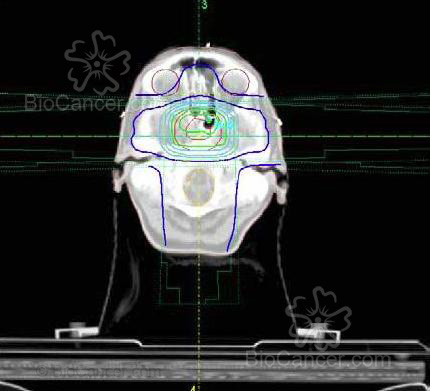

Imagen sagital a partir de cortes de TAC donde se puede ver la reconstrucción del volumen blanco de un tumor hipofisario (rojo claro) con las multiláminas que conforman el campo de irradiación (amarillo) con 1-1.5 cm de margen alrededor del volumen blanco

Figura 1. Imagen sagital a partir de cortes de TAC donde se puede ver la reconstrucción del volumen blanco de un tumor hipofisario (rojo claro) con las multiláminas que conforman el campo de irradiación (amarillo) con 1-1.5 cm de margen alrededor del volumen blanco.

Imagen de un corte axial del TAC de dosimetría donde se aprecia las distintas isodosis de distribución de la radiación sobre el cerebro: rojo interior = volumen tumoral; rojo exterior = margen de +/- 1.5 cm; verde interior = isodosis del 100%; verde exterior = isodosis del 95%; azul  clara interior = isodosis del 90%

Figura 2. Imagen de un corte axial del TAC de dosimetría donde se aprecia las distintas isodosis de distribución de la radiación sobre el cerebro: rojo interior = volumen tumoral; rojo exterior = margen de +/- 1.5 cm; verde interior = isodosis del 100%; verde exterior = isodosis del 95%; azul clara interior = isodosis del 90%.

emplean fraccionamiento altos (altas dosis/día) y en diversas estructuras intracraneales. La dosis de irradiación para enfermedad subclinica (microscópica o sospechada pero no visible) es de 45-50 Gys (Figuras 1 y2).

RT Localizada: es el procedimiento más habitual para los tumores primarios. En los tumores de alto grado se recomienda englobar el tumor prequirúrgico más un margen de 3 a 4 cm en el campo inicial, con una reducción (sobreimpresión o boost) en la parte final del tratamiento con un margen de 1.5-2 cm. En los tumores de bajo grado el margen habitual es de 1.5-2 cm durante todo el ttº. No obstante, con las técnicas actuales de planificación tridimensional, en los tumores con bajo riesgo de recurrencia (meningiomas, craneofaringiomas y tumores hipofisarios) se están empezando a dejar márgenes menores, de +/- 1-1.5 cm, que incluso se pueden llegar a márgenes menores de 5 mm cuando se emplean técnicas apropiadas de inmovilización y estereotaxia.